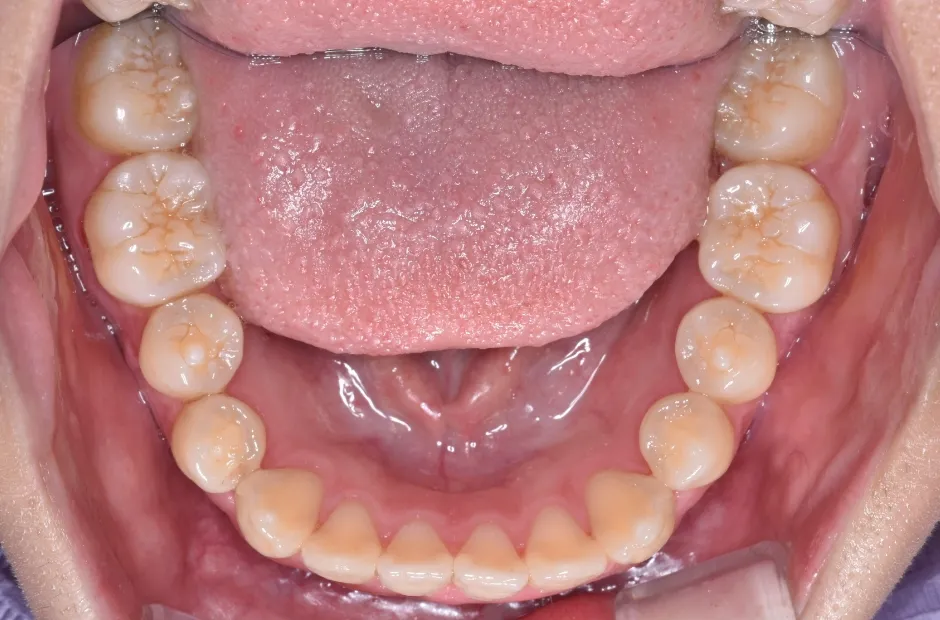

叢生

| 診断名・主訴 | 叢生 |

|---|---|

| 年齢・性別 | 43歳・女性 |

| 治療期間・回数 | 2年7か月 27回 |

| 治療に用いた主な装置 | 舌側矯正 |

| 抜歯部位 | 両顎4,4 |

| 治療費 | 100万円(税抜) |

| リスク・副作用 | 装置による違和感・疼痛・歯肉退縮・歯根吸収・虫歯のリスクなど |